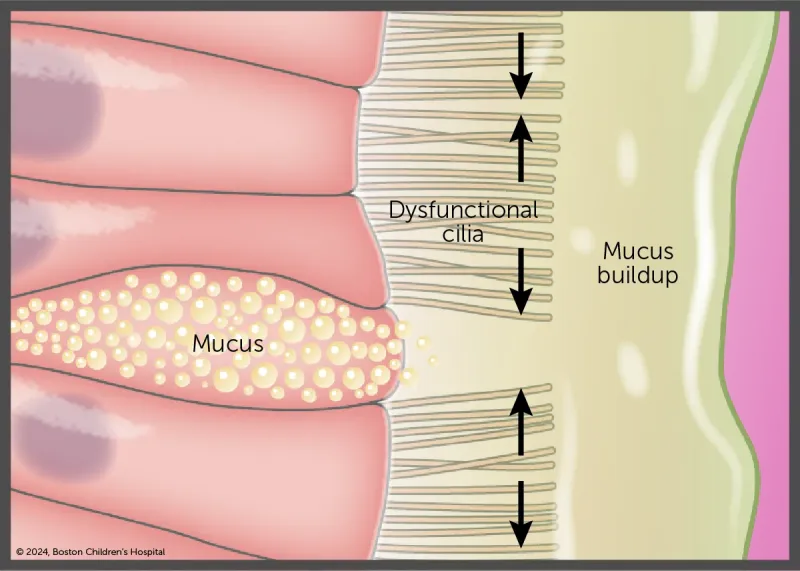

Primary ciliary dyskinesia (PCD) is a disorder of the cilia that line the entire respiratory tract, including the middle ear, sinuses, airway, and lungs, as seen in this illustration.